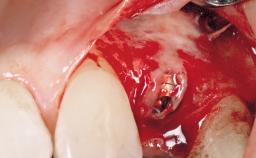

The video demonstrates implant placement using a surgical stent according to the principle of prosthodontically driven implant placement. The deficient ridge is augmented with locally harvested autologous bone chips, a superficial layer of xenogenic DBBM particles and a resorbable collagen membrane. The surgery is completed with a precise, tension-free primary wound closure.

The case concludes with the presentation of the final prosthesis and the esthetic outcome, demonstrating stable soft tissue conditions and stable bone crest levels at the 3-year follow-up.